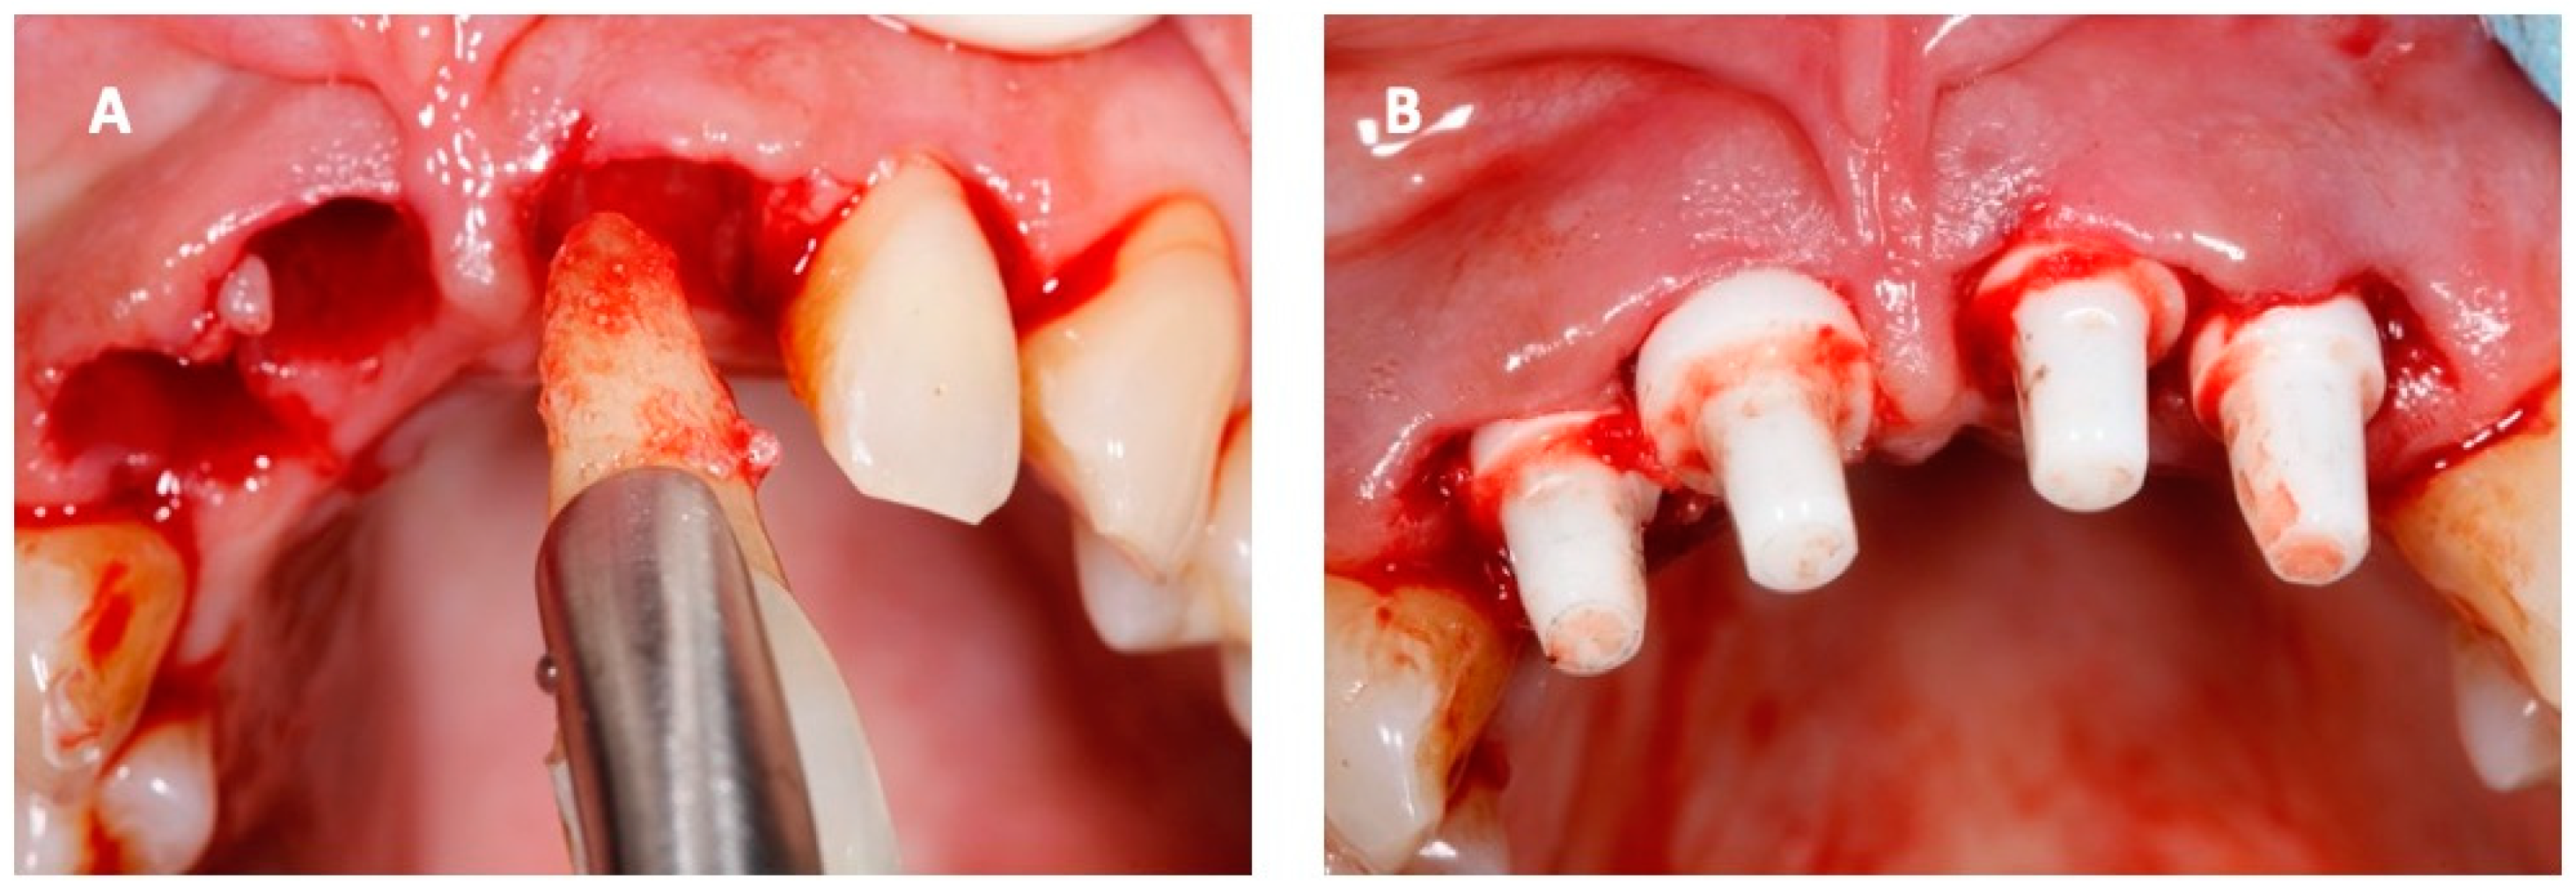

2. Case Report